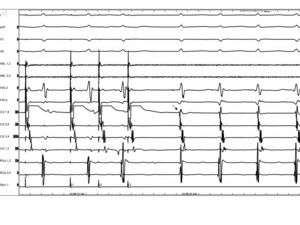

AVNRT Slow/Fast

EKG